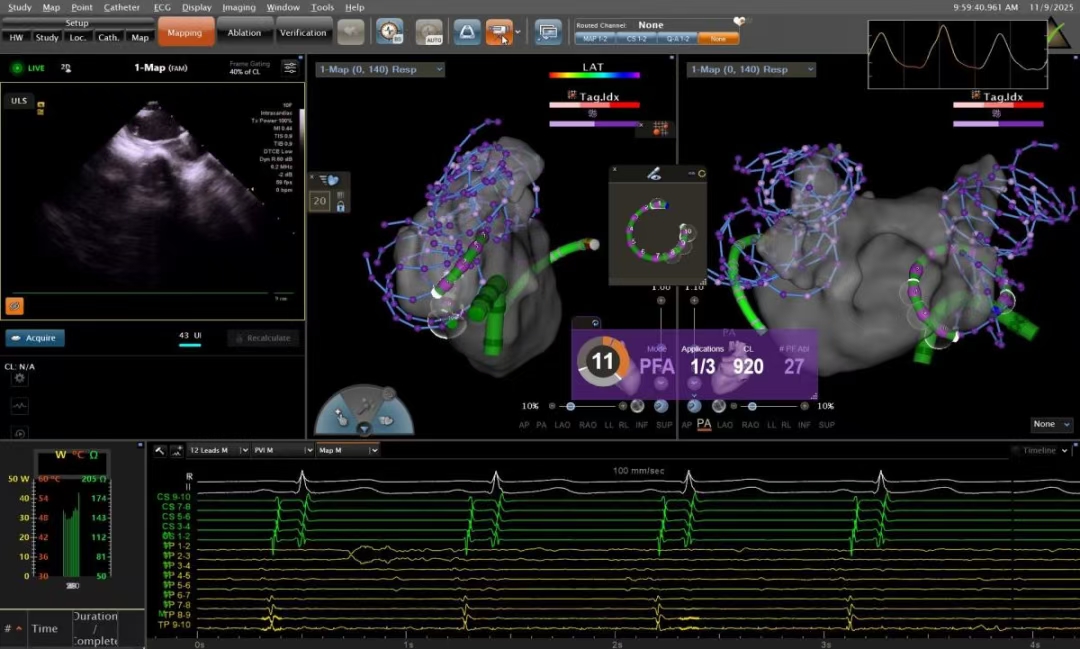

本次手术采用的VARIPULSE脉冲消融技术,结合三维电生理标测系统(CARTO 3),实现了对心脏解剖结构的实时重建与消融路径的全程可视。该系统能精准定位病灶,最大限度保护周围正常组织,提高手术成功率的同时,也显著降低了传统消融方式可能带来的风险。

禁忌书屋 心血管内科主任钟江华介绍:“VARIPULSE导管与三维系统配合,能实时监测导管与心肌的贴靠情况,配合超声引导穿刺,使操作更自如,能量释放更集中。这样既减少了术中溶血风险,也提高了肺静脉隔离的成功率,从技术上为患者多加了一重安全保障。”

患者获益:手术1.5小时实现“绿色”精准治疗

团队核心电生理术者——张伟在回顾该病例时指出,本次手术全程0射线,依赖超声自动建模,实现了“绿色”电生理操作。整台手术耗时约1.5小时,其中肺静脉隔离关键步骤仅需约20分钟。患者术后恢复良好,次日即可下床活动,真正体现了“高效、安全、微创”的现代治疗理念。

术中房颤发作图